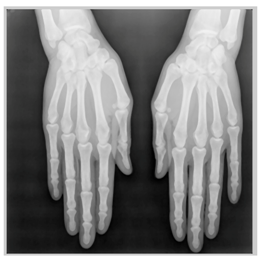

In this section, we present and analyze the results obtained with the proposed method, and compare it to methods proposed in similar works. The proposed watermarking system is implemented using MATLAB and executed on a Windows machine with the following characteristics: Intel R Core i5 processor, 4 GHz, 4 GB RAM, and Microsoft Windows 8 Professional operating system platform. In our experiments, we have used DICOM images of size 512 × 512 pixels as shown in Table 1.

Table 1.

Original images.